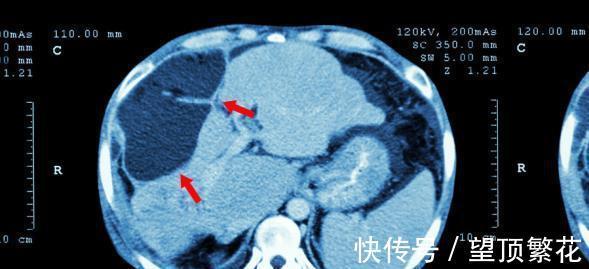

经过医生检查后,发现杨大姐转氨酶数量偏高,肝脏硬度中位数超出正常指标,初步判断是肝硬化初期,所幸发现较早,还有治愈的可能。